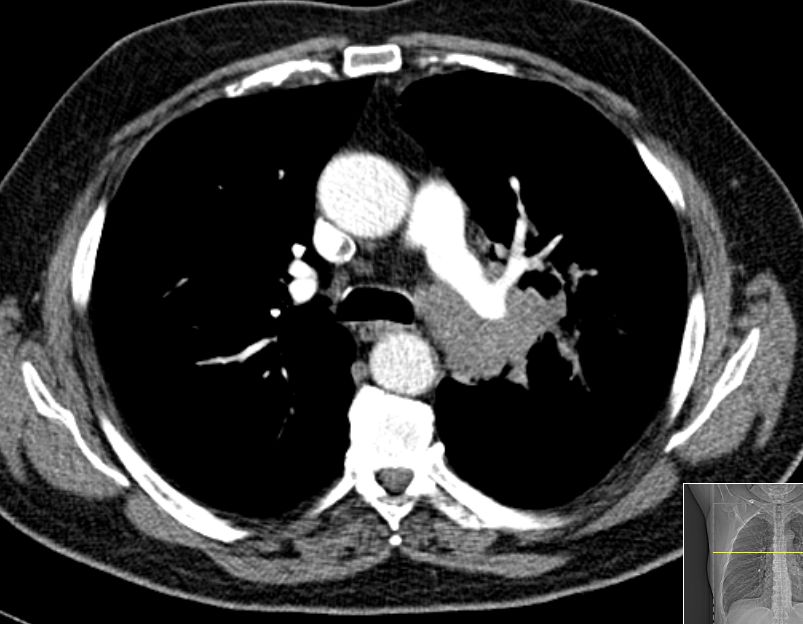

64-jähriger Mann mit plötzlich aufgetretener Luftnot. Inzwischen Sauerstoff - abhängig.![]() |

![]() | |||